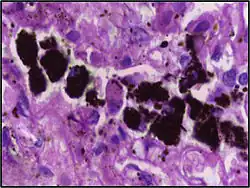

Alveolar macrophages are frequently seen to contain granules of exogenous material such as particulate carbon that they have picked up from respiratory surfaces. Such black granules may be especially common in smoker's lungs or long-term city dwellers.

| Anthracosis | Black-brown granules | Interstitium (perivascular) | ![]() |

Black arrow shows interstitial anthracotic pigment. Nearby macrophages (white arrow) can be presumed to contain anthracotic pigment. | ||

| Respiratory bronchiolitis | "Smoker’s macrophages" | Yellow to light brown and finely granular[4] | Airways (especially respiratory bronchioles) | Tobacco smoking | ![]() |

Smoker's macrophage in center |

| Chronic pulmonary congestion | Siderophages | Brown-golden and refractile.[5] | Alveoli[6] |

|

![]() |

Siderophage (black arrow), and interstitium with edema, hemosiderin deposition (black arrow) and collagenous thickening, indicating heart failure. |